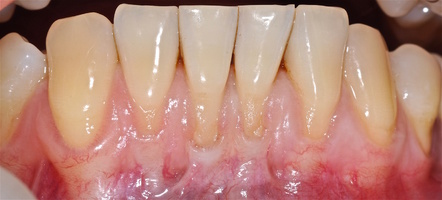

Во всех случаях применения аутотрансплантата и ТМО (dura mater) наблюдается сопоставимый положительный клинический результат по всем параметрам оценки рецессий десны (табл. 4). В случае нескольких зубов в области наиболее глубоких рецессий с наименьшими клиническими показателями имеет место сохранение класса рецессии не более первого класса (9 зубов) и глубиной не более 2 мм, 1.6 зуб — 3 мм.

В зарубежной литературе встречается также совокупный показатель эффективности лечения рецессий десны — процент закрытия корня зуба — отношение разница между конечным и исходным значениями глубины рецессии к исходному значению в процентах. Положительный результатом лечения является значение равное или более 80% [4]. Использование только показателя глубины рецессии десны для анализа эффективности лечения без учета остальных показателей (ТКД, ШКД, РРД, ЗДК) не дает полной картины результата и может быть применимо только в совокупности с другими показателями (рис. 6а-й).

Так в нашем случае процент закрытия корня зуба наблюдается больше 80% у 13 зубов. Менее 80% — у 11 зубов. Это связано с сохранением класса рецессии после лечения в области зубов с наибольшим классом рецессии и наибольшим показателем глубины рецессии. При этом средний показатель всех 24-х оперированных зубов — 83,1%. При этом среднее значение процента закрытия корня зуба для зубов с положительным результатом (более 80%) составляет 96,65%. Среднее значение для результатов менее 80% — 54,73, что связано с изменением глубины рецессий с 6 мм до 3 мм, с 4 мм до 2 мм и с 2 до 1 мм. При этом для аутотрансплантата и для ТМО результаты сопоставимы.